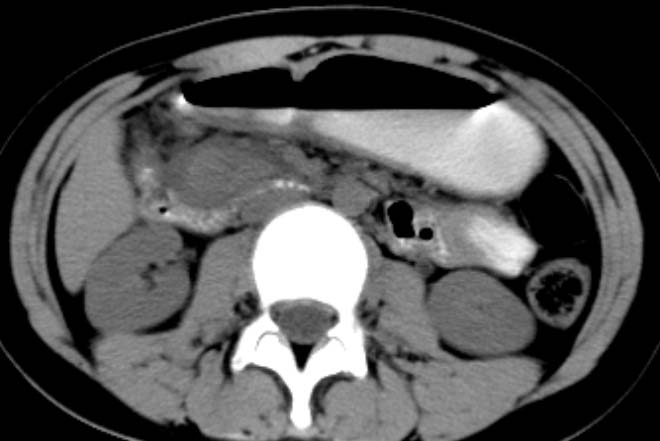

女,14岁。腹痛3天。腹部触诊未触及包块。碘剂阳性未增强。求助战友。。。。。。。。。。。

胰头部明显肿大,胰周间隙浸润,考虑胰腺炎可能性大

胰头部增大,周围模糊,有渗出,胰腺炎可能性大,建议结合化验检查;左侧输尿管上段略扩张.

胰头部明显肿大,胰头周脂肪密度加大。十二指肠环扩大受压。胰管未见确切扩张。考虑胰腺炎可能性大。建议增强扫描。

胰头部增大,周围结构模糊,并明显见渗出。支持:急性胰腺炎!

胰头明显肿大呈肿物样,周围脂肪密度增高,结合病人年龄及临床表现,首先考虑炎性改变,建议结合实验室检查明确。必要是复查或mr检查

病灶应在胰头下区,不一定是胰头,结合周边低密度水肿,是否可能为十二指肠(xi)室炎症或其它炎症。